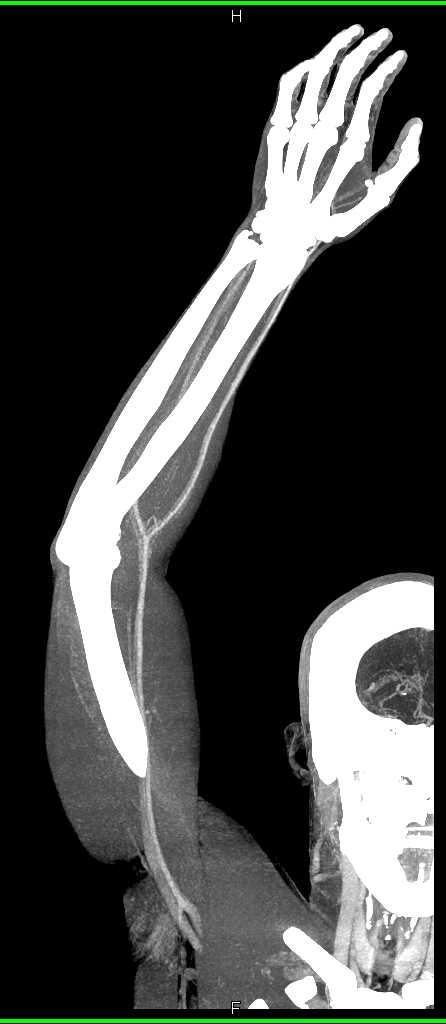

GSW with Bleed Near Knee